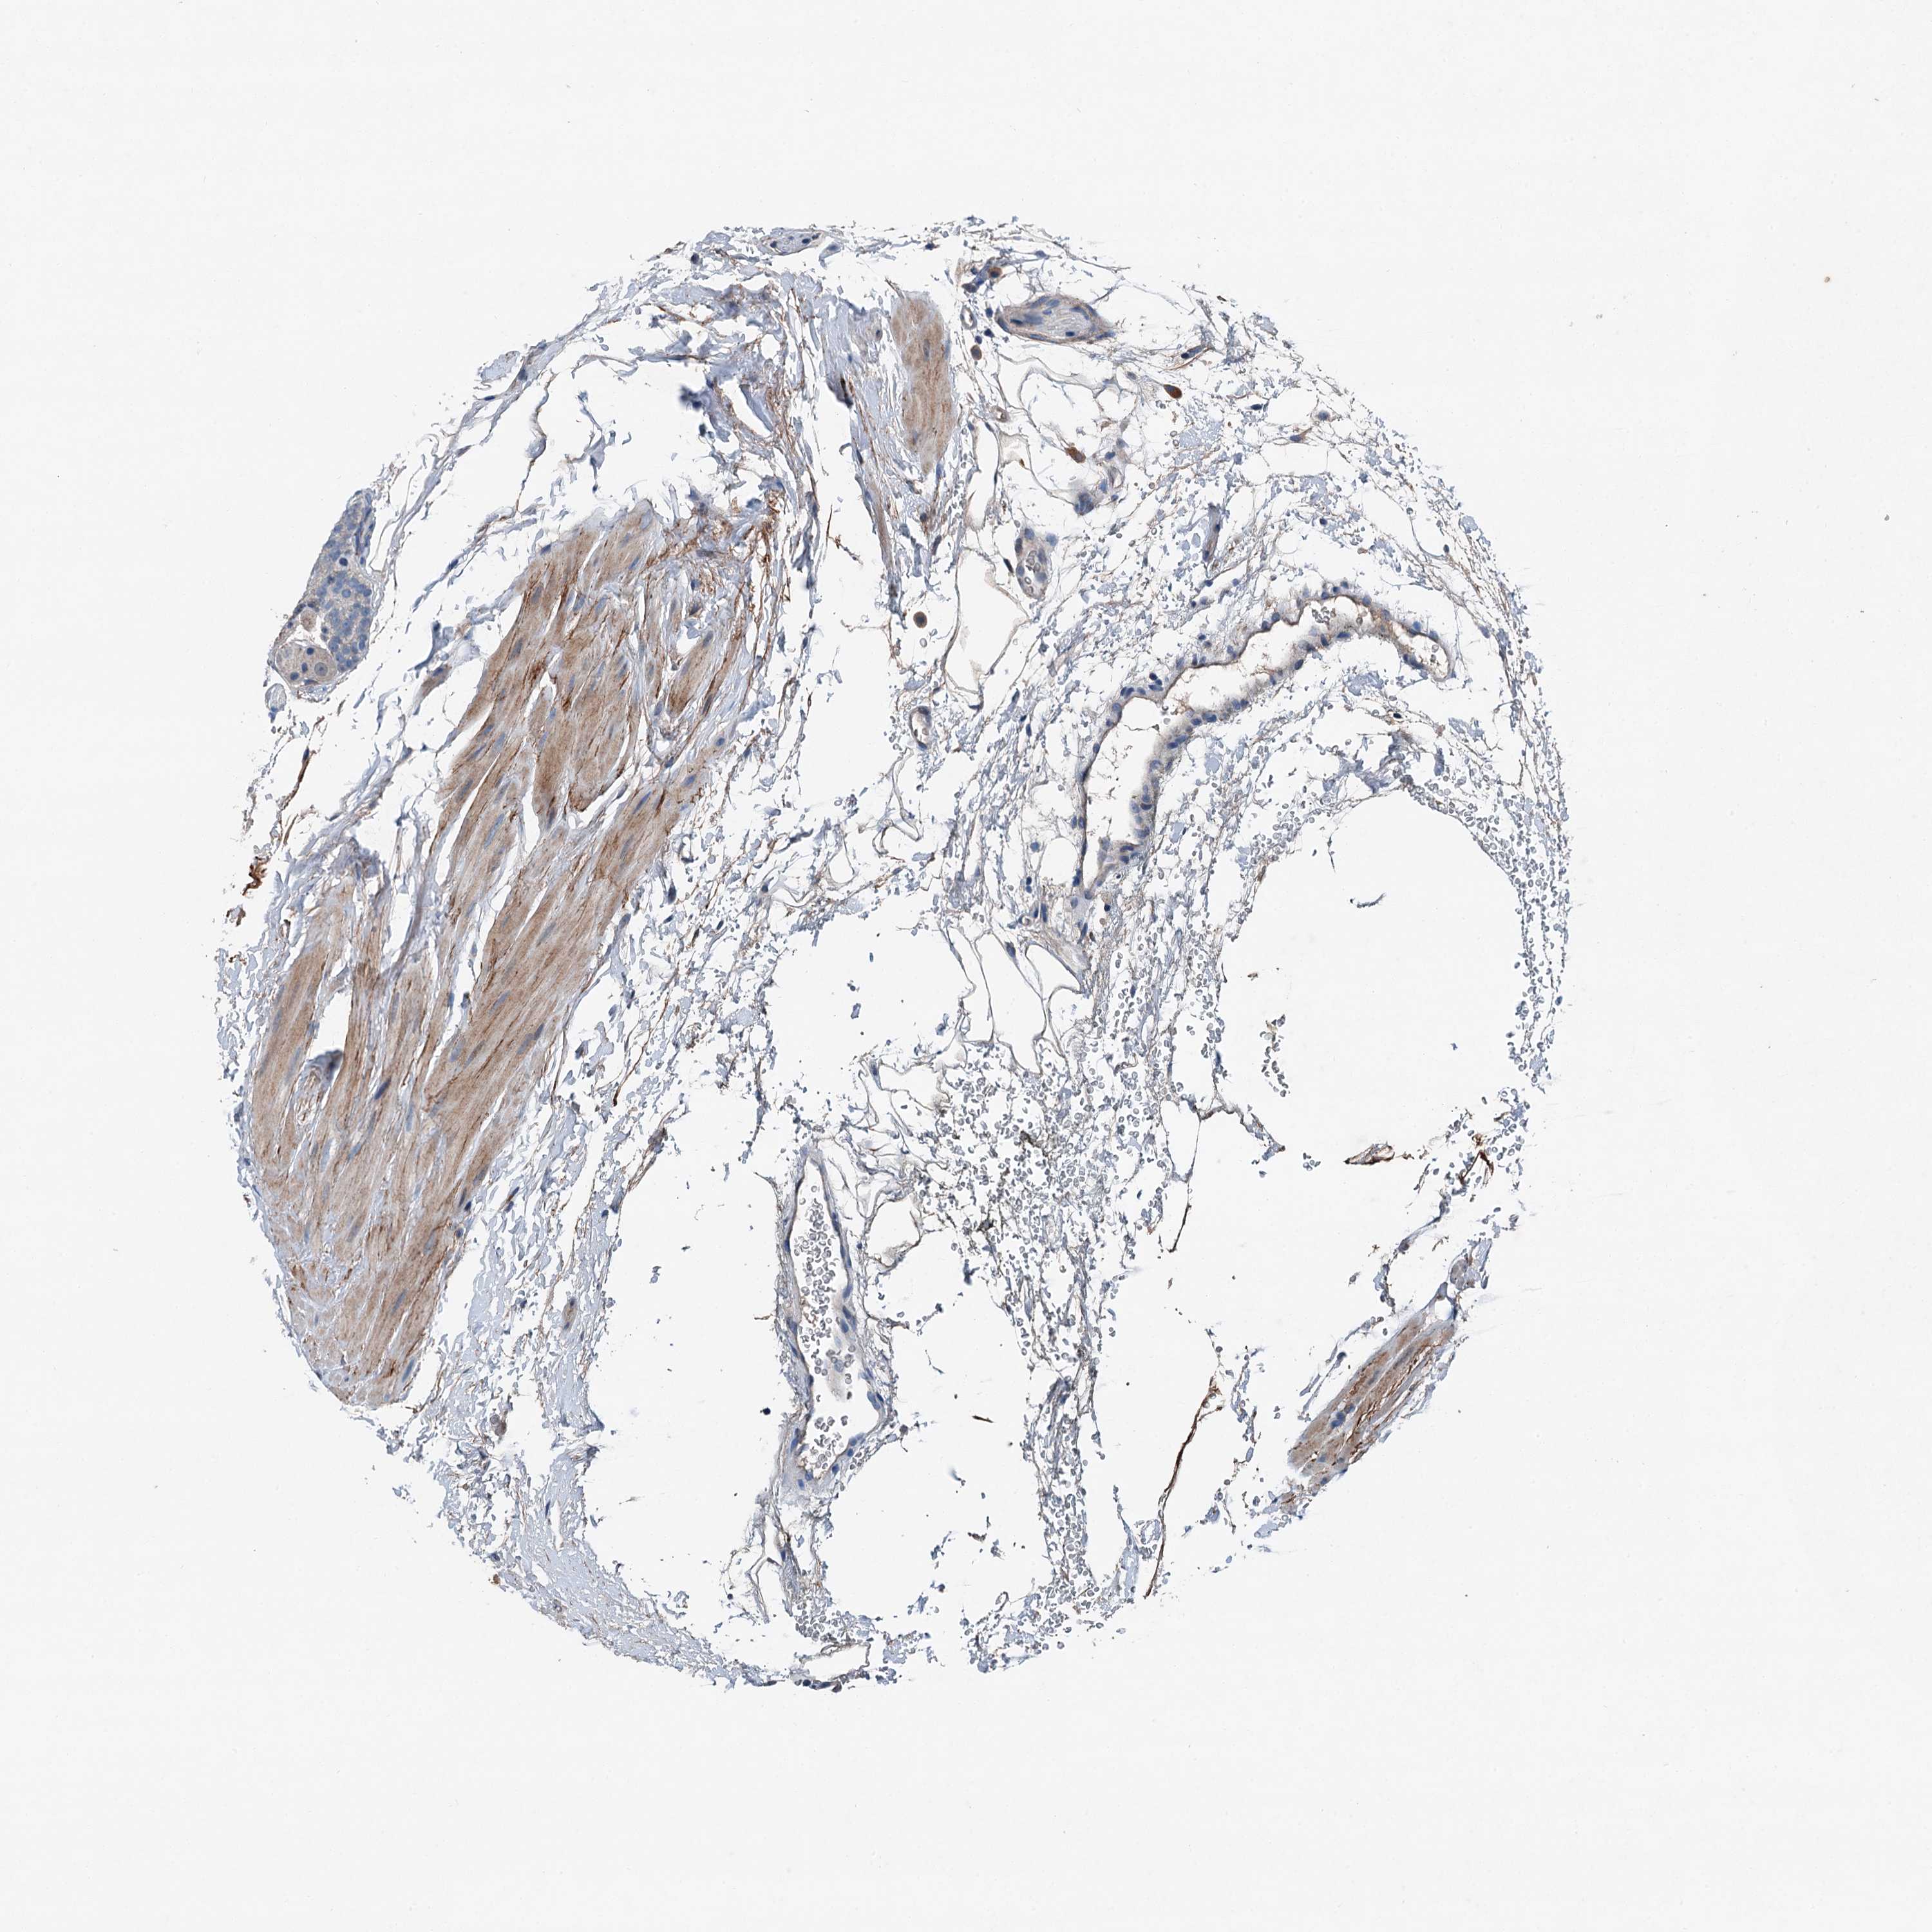

PROSTATE CANCER - Protein expressioni

A mouse-over function shows sample information and annotation data. Click on an image to view it in a full screen mode. Samples can be filtered based on level of antibody staining by selecting one or several of the following categories: high, medium, low and not detected. The assay and annotation is described here.

Note that samples used for immunohistochemistry by the Human Protein Atlas do not correspond to samples in the TCGA dataset.

Antibody stainingi

Antibody staining in the annotated cell types in the current human tissue is reported as not detected, low, medium, or high, based on conventional immunohistochemistry profiling in selected tissues. This score is based on the combination of the staining intensity and fraction of stained cells.

Each image is clickable and will lead to virtual microscopy that enables deeper exploration of all samples and also displays staining intensity scores, fraction scores and subcellular localization as well as patient and tissue information for each sample.

Antibody HPA041015

Staining

High

Medium

Low

Not detected

Intensity

Strong

Moderate

Weak

Negative

Quantity

>75%

75%-25%

<25%

None

Location

Nuclear

Cytoplasmic/membranous

Cytoplasmic/membranous,nuclear

Adenocarcinoma, High grade

Adenocarcinoma, Low grade